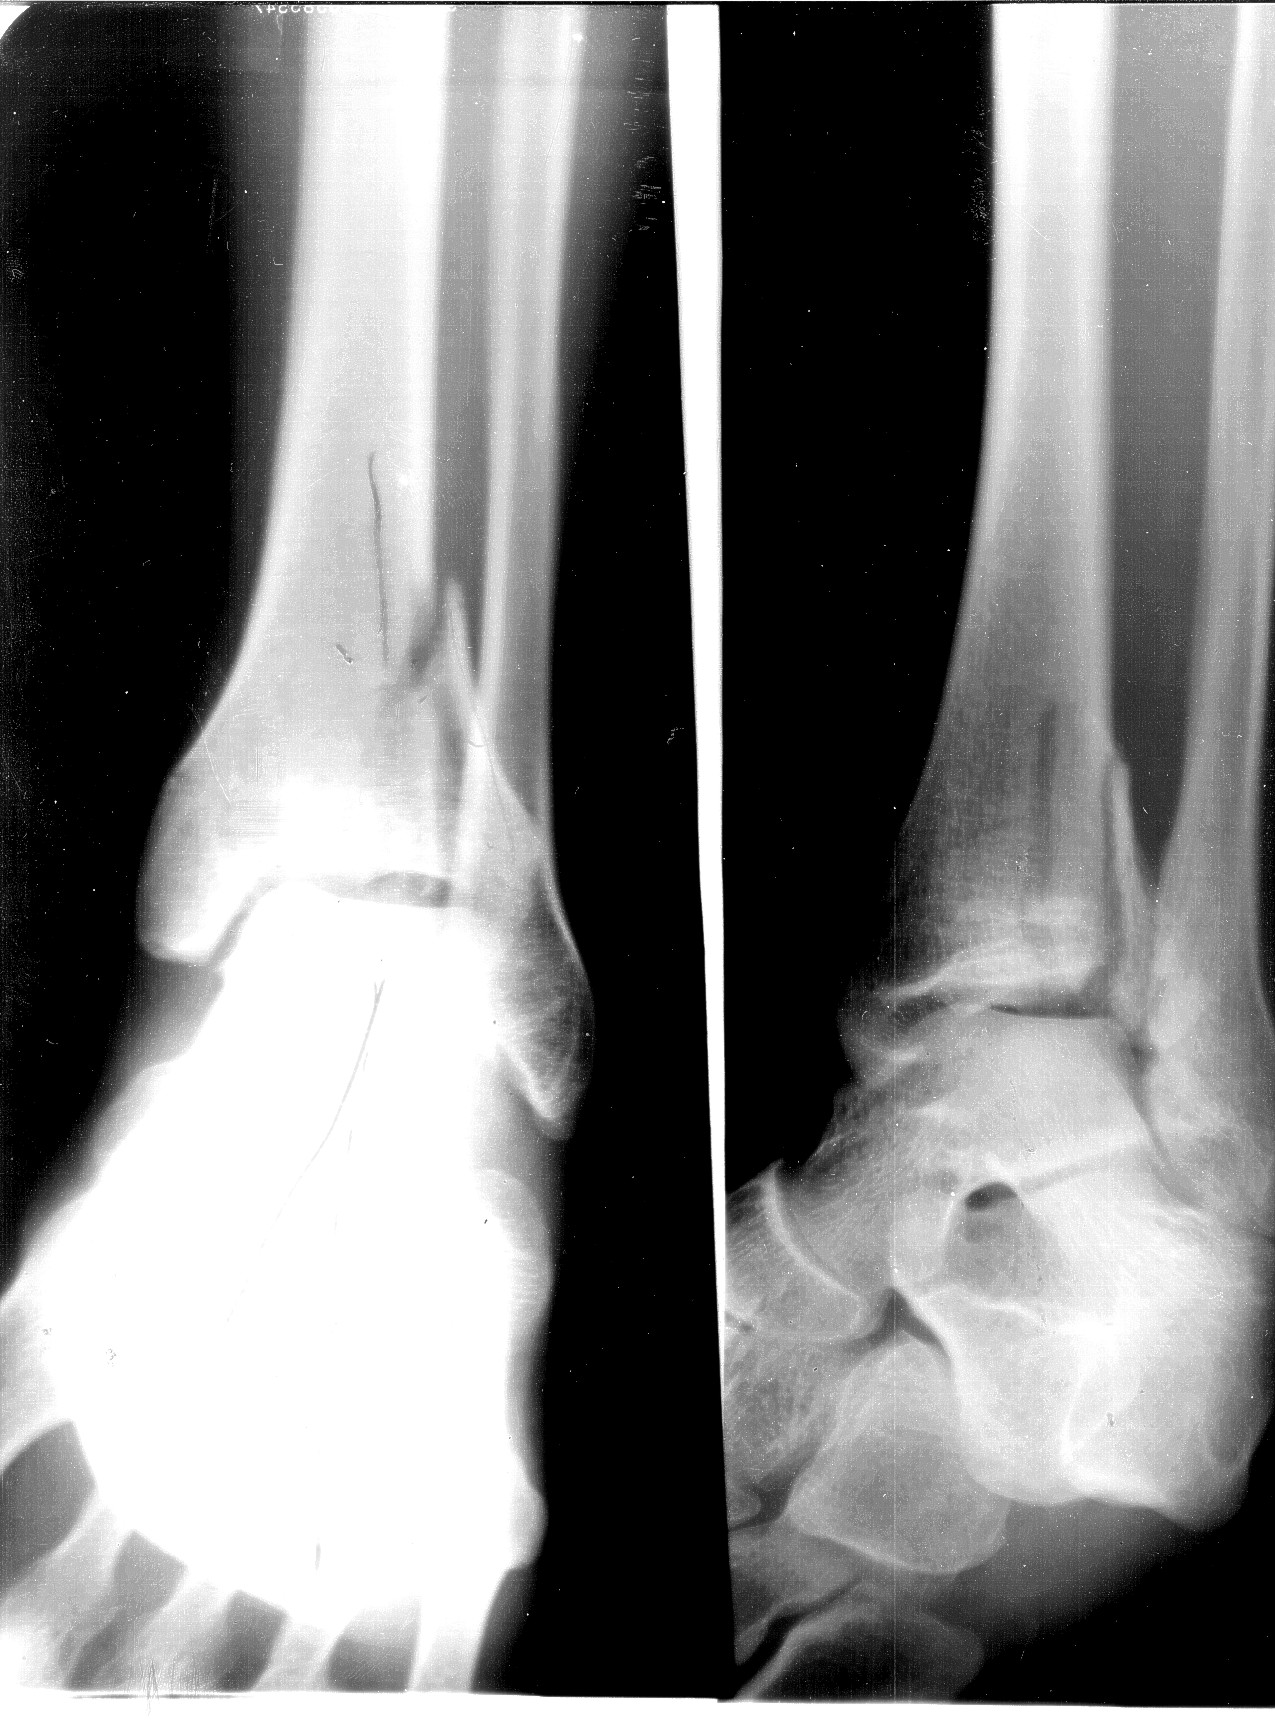

[IMG]xray1-eh.jpg2020-01-26 20:40 428K